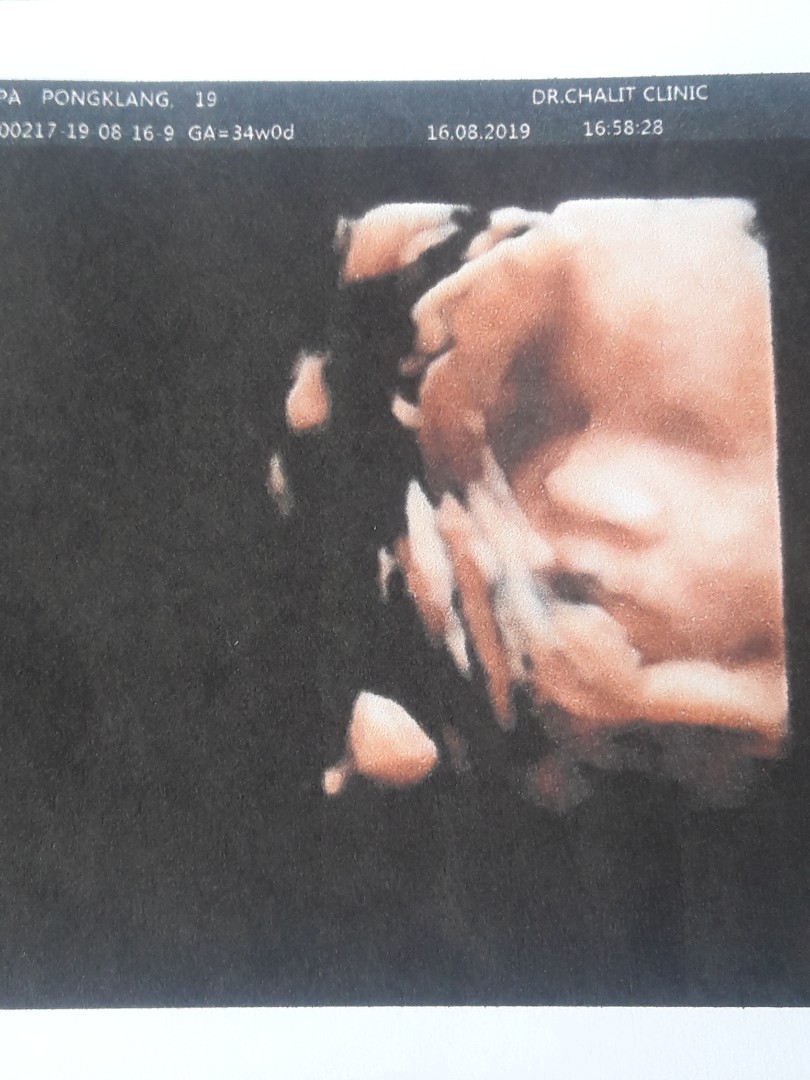

32 weeks คร้าฟๆๆ นู๋ชื่อบีลิฟ

ตอน 26สัปดาห์ค่ะ เพศชาย